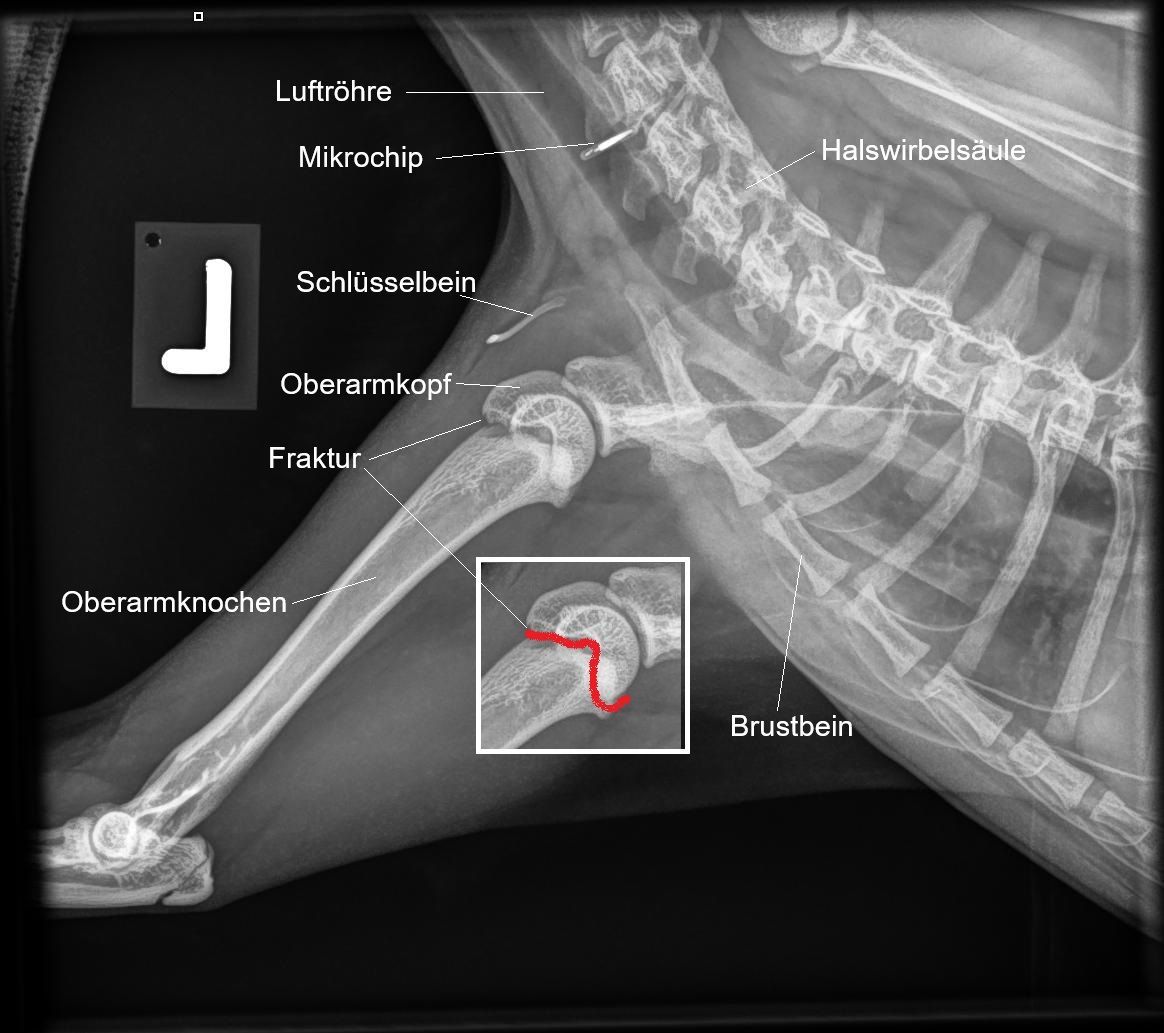

Oberarmkopf-Fraktur bei einer Jungkatze

ZELDA, Hauskatze, weiblich-kastriert, 8 Monate alt

Seit dem Vortag belastet die junge Kätzin ihr linkes Vorderbein nicht mehr. Die Besitzer haben schon Schmerzmittel verabreicht, was aber das Problem nicht gelöst hat. Da die Katze Freigang geniesst, besteht der Verdacht, dass sie einen Unfall erlitten hat

Untersuch und Röntgen

Die Katze weist äusserlich keine Wunden auf. Beim Abtasten scheint das Tier aber in der Schultergegend schmerzhaft; bei der Manipulation des Schultergelenks ist ein reibendes Gefühl feststellbar (sogenannter Krepitus). Wir fertigen Röntgenbilder des linken und zum Vergleich des gesunden rechten Vorderbeines an.

Andererseits weisen die Knochen sogenannte Wachstumsfugen (Epiphysenfugen) auf. In diesen Zonen am Ende der Knochen findet das Längenwachstum statt; sie bestehen aus weniger stabilem Knorpelgewebe. Im Zuge des Wachstums verkalkt das neugebildete Knorpelgewebe zu Knochengewebe; am Ende des Wachstums verkalken dann auch die Wachstumsfugen selbst. Im Röntgen sind diese Wachstumszonen als schwarze Striche erkennbar - hier ist der Knochen weniger röntgendicht.